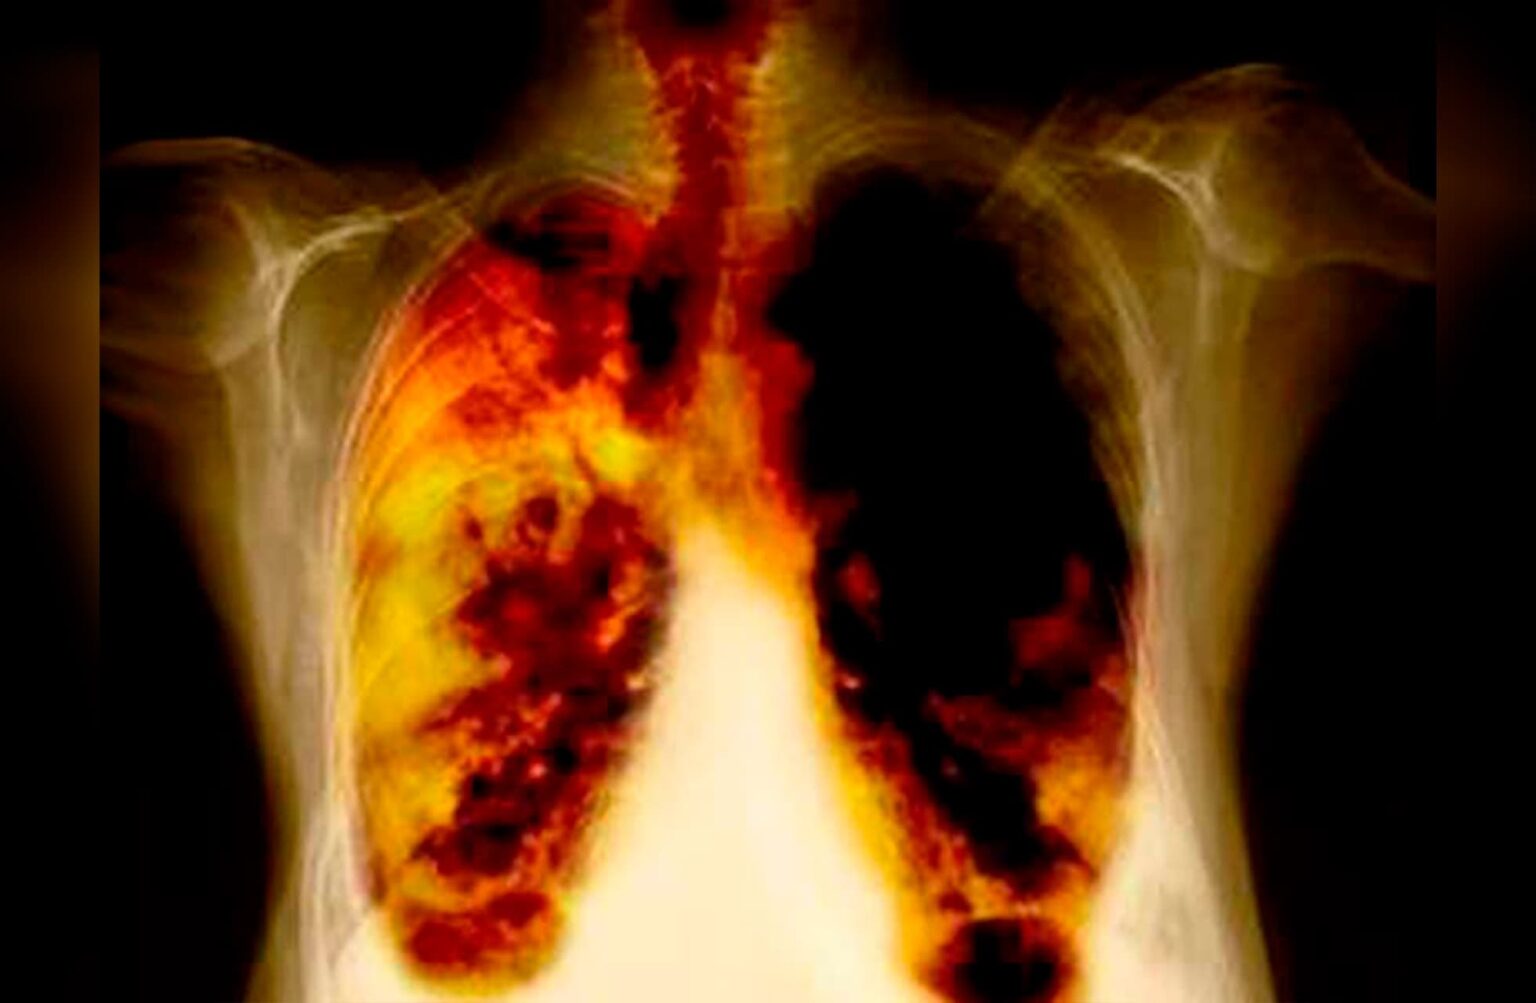

Investigadores de la Universidad de Navarra dieron a conocer que han logrado que los tumores de pulmón resistentes a la inmunoterapia respondan a tratamiento.

Los especialistas aseguran en su investigación que han descubierto en una proteína -identificada como DSTYK- el ‘talón de Aquiles’, es decir, el punto débil, para este tipo de tumores con la inhibición de dicha molécula involucrada en el desarrollo tumoral de estos órganos vitales.

Imagen: UNAM

Foto: Universidad de Navarra